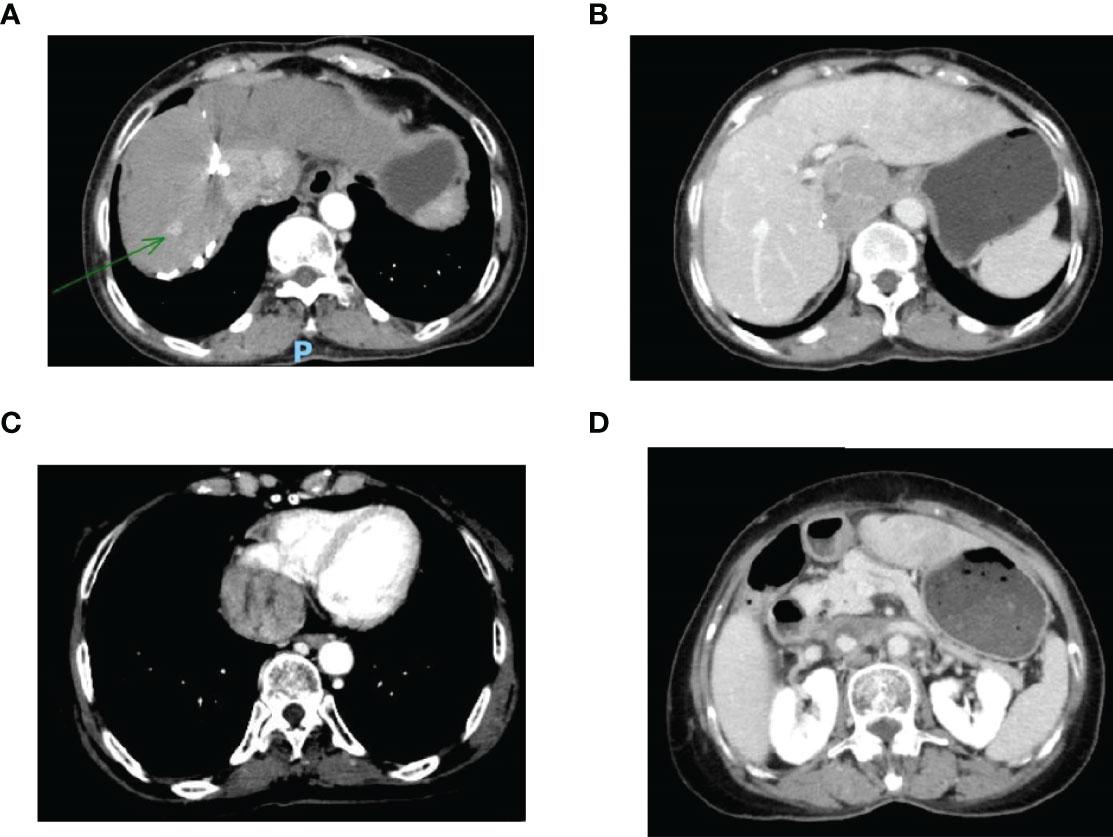

This case report was conducted per the CARE Guidelines (17). In July 2021, a 66-year-old Chinese woman was hospitalized due to severe bilateral lower extremity edema and palpitation, without any accompanying symptoms, such as abdominal pain or bloating. She had no history of high blood pressure, diabetes, or hepatitis. She had been diagnosed with HCC nine years ago and had undergone surgical resection. Postoperative pathology revealed a highly differentiated HCC. She had received radiofrequency ablation because of local HCC recurrence in November 2013 and May 2014. Subsequently, the patient did not undergo medical examination until July 2021. In July 2021, an enhanced computed tomography (CT) showed HCC recurrence at the junction of the anterior segment (S5/S8) of the liver, with approximately 1.8 × 1.4 cm size. The mass wrapped and invaded the adjacent IVC and grew into the IVC, RA, and left renal vein. The diagnosis was HCC with RA and IVC tumor thrombi with Barcelona clinic liver cancer (BCLC) stage-C (Figure 1). Then, the patient received sorafenib treatment and developed grade 4 (the US National Cancer Institute Common Terminology Criteria for Adverse Events [CTCAE v4.03]) skin rash and discontinued the sorafenib treatment. Hormones and proglobulin were used to treat dermatitis, and adverse skin reactions were reversed. According to a published study, radiotherapy can be used to treat liver cancer with RA and IVC tumor thrombi (18). Moreover, immunotherapy plus radiotherapy and antiangiogenic therapy is a safe and effective approach for advanced HCC (19). Therefore, we administrated radiotherapy, immunotherapy, and lenvatinib. The patient received radiotherapy in August 2021 through volumetric modulated arc therapy and respiratory gating technology. The dose for HCC recurrence was 50 Gy/25 fractions and for HCC with RA and IVC tumor thrombi was 45 Gy/25 fractions (Figure 2). She simultaneously received pembrolizumab (100 mg; 2 mg/kg, q3w) and lenvatinib (8 mg/day). Lower extremity edema and palpitations resolved after radiotherapy. Toxicity was well tolerated with no liver toxicity, and grade ≥ 3 adverse events were observed. After four cycles of pembrolizumab plus lenvatinib treatment, the CT scan indicated that the patient had a partial response and a decreased thrombus according to the Response Evaluation Criteria in Solid Tumors (RECIST) v.1.1. The HCC lesion at the junction of S5/S8 segment disappeared, and the IVC/RA thrombus decreased in size (Figure 3). No disease progression was observed. The patient continued to receive the pembrolizumab plus lenvatinib treatment (the last pembrolizumab treatment day was March 26, 2022). The patient remained stable at the time of writing (> 7 months). During the treatment period, there was no grade ≥ 3 adverse events or liver toxicity. Leukopenia (grade 2), thrombocytopenia (grade 1), hypoalbuminemia (grade 1), and hypertension (grade 2) were resolved using symptomatic drug treatment. Granulocyte colony-stimulating factor was administered to deal with white blood loss. A CT scan was regularly performed for every 3 months. Blood routine, liver function, kidney function, electrolyte, thyroid function, and pituitary function were regularly measured. The timeline scheme of the major clinical events of the patient since HCC diagnosis is shown in Figure 4.

Figure 1 (A) Enhanced CT revealed a mass tumor in the S5/S8 segment of the liver; (B) The tumor thrombus in the inferior vena cava; (C) The tumor thrombus in the right atrium; (D) The tumor thrombus in the left renal vein. CT, computed tomography.